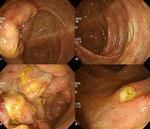

44세 여자 환자로 내원 3주 전부터 발생한 발열 및 1주 전부터 발생한 설사를 주소로 내원하였다. 최근 여행력은 없었으며, 과거력에서 특이 소견은 관찰되지 않았으나, 3주 동안 약 3 kg 정도의 체중 감소를 호소하였다. 이학적 검사에서 혈압 110/70 mmHg, 심박동 94회/분, 체온 38.3 oC 였고, 혈액 검사에서 WBC 2,900/mm3, Hb 11.4 g/dL, platelet count 152,000/mm3 이었고, albumin 3.4 g/dL, AST/ALT 68/49 IU/L, LDH 835 IU/L, CRP 10.1 mg/dL (참고치 < 0.5) 이었다. 복부 전산화 단층 촬영술(그림 1)을 시행하였고, 대장내시경(그림 2)을 시행하였으며, 조직 검사에서 그림 3과 같은 소견이 관찰되었다. 진단은?